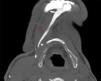

Se realizó una gammagrafía ósea que demostró una captación localizada de tecnecio en el maxilar inferior. Se realizó posteriormente una tomografía computarizada del cuello, la proyección axial maximum intensity projection (MIP) (fig. 1) y las imágenes en reconstrucción 3D (fig. 2) muestran una calcificación lineal anormal que se extiende desde el borde inferior de la mandíbula hacia el hioides, siguiendo el vientre anterior del músculo digástrico.